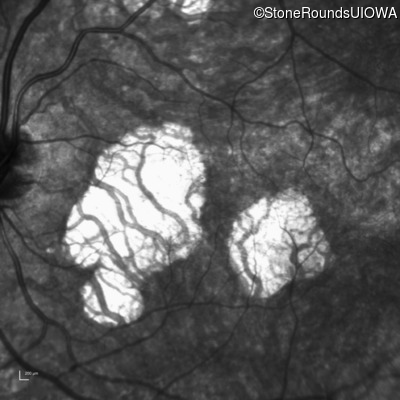

Infrared Fundus Photograph - Left - 20/30 +1 sc

Exemplar